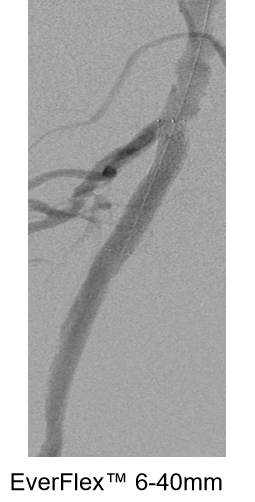

对于长段、严重钙化的股浅动脉病变,

巧克力球囊并不能完全避免夹层的发生

长段(≥20cm)、严重钙化(钙化评分≥3 分)的股浅动脉病变,因钙化范围广、质地坚硬且常伴随血管迂曲,巧克力球囊虽能降低夹层风险,但无法完全避免 —— 核心原因在于病变本身的复杂性与器械技术边界,临床需通过 “联合策略” 进一步提升安全性与疗效。

Chocolate 5-120mm

巧克力球囊扩张后

出现的夹层